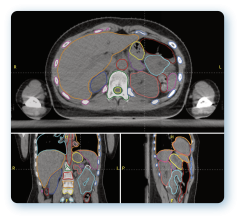

March 24, 2014 — Medical physicists met in Denver, Colo., March 15-18 for the American Association of Physicists in Medicine (AAPM) Spring Clinical Meeting, hosted at the Denver Marriott Tech Center. The meeting focused on helping medical physicists with the integration of emerging technologies into the clinical environment. Mirada Medical demonstrated its comprehensive suite of advanced deformable image registration (DIR) software tools to meeting attendees. The company utilizes its scientifically advanced DIR algorithms to provide practical tools to support treatment planning.

Mirada’s scientists have made their algorithms application and modality specific — carefully tuning internal parameters, such as deformable field smoothness, degree of freedom and similarity function sensitivity. This provides a strong basis for multi-modality contouring, auto contouring, dose deformation and composite dose, and it provides support for adaptive therapy and re-treatment decisions.